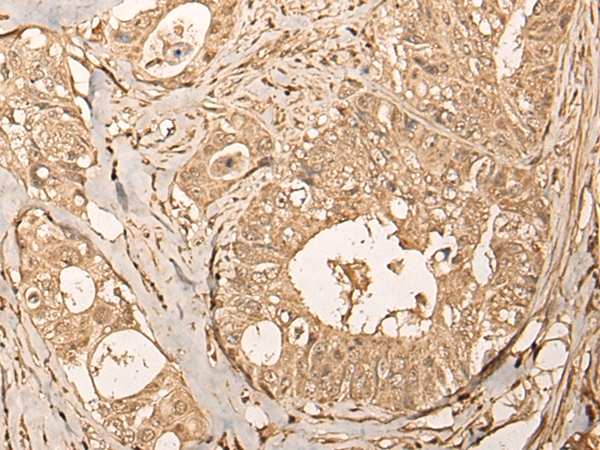

The image on the left is immunohistochemistry of paraffin-embedded Human colorectal cancer tissue using 46701(UTP11 Antibody) at dilution 1/30, on the right is treated with fusion protein. (Original magnification: x200)